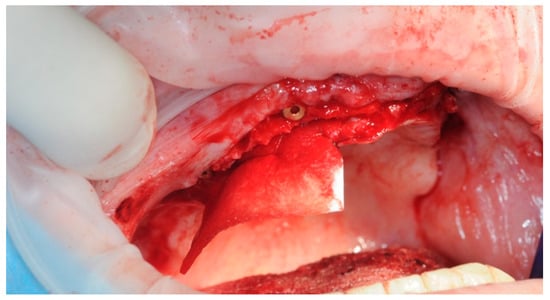

2.3. Re-Entry Surgery